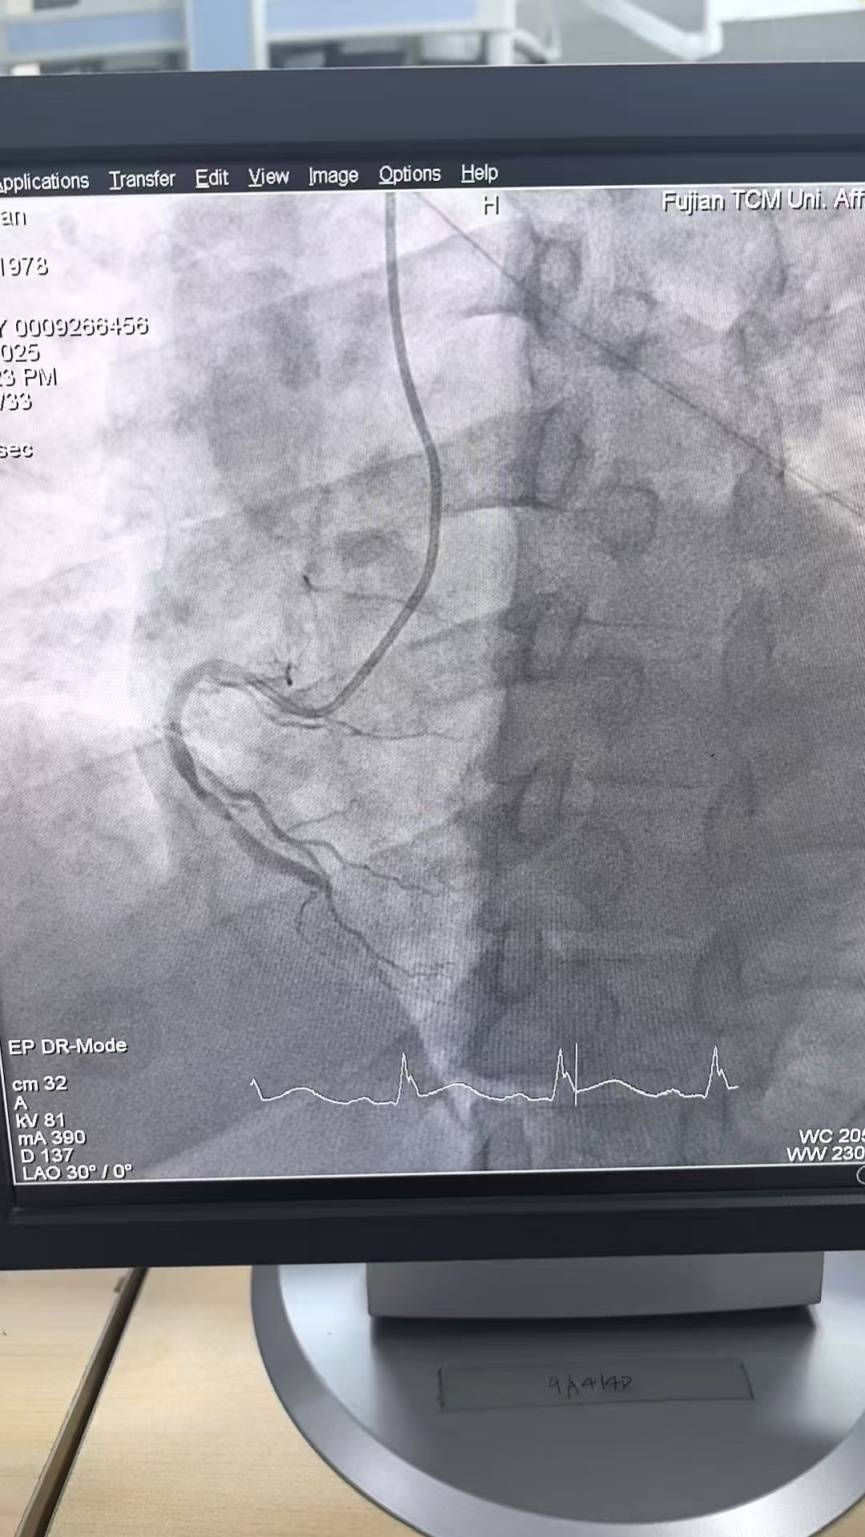

11月20日 是第12个“中国心梗救治日” 这几天 福州降温,心梗患者增多 福建省人民医院心血管科副主任医师林培森提醒:每当听到“断崖式降温”,心血管疾病人群就要警惕,因为寒潮来袭不仅仅是“冻手冻脚”